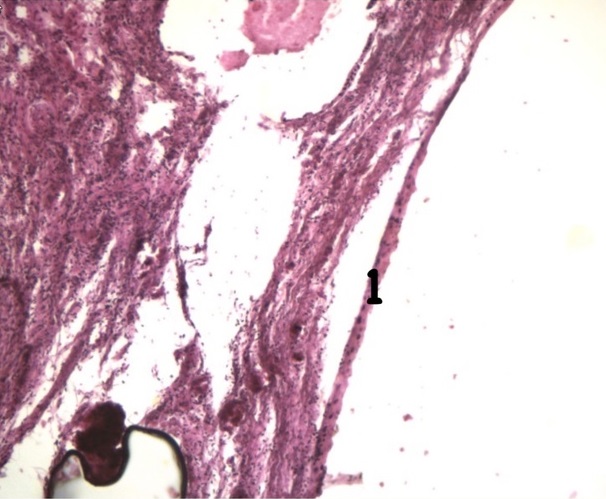

Дисплазия – это патологический процесс, при котором в толще покровного эпителия шейки матки появляются клетки с различной степенью атипии с последующим изменением стратификации эпителия без вовлечения стромы в патологический процесс. Дисплазия относится к предраковым состояниям, предшествующим развитию рака in situ и инвазивного рака шейки матки . Типичная локализация дисплазии у молодых женщин – это вагинальная часть шейки матки, с возрастом наблюдается тенденция к расположению ее на эндоцервиксе. Согласно многоцентровым эпидемиологическим исследованиям, максимальное количество инфекционных поражений шейки матки в возрасте 18–30 лет, а пик дисплазии и преинвазивного рака – 30–39 лет .

Рисунок 2 - Дисплазия эпителия слизистой оболочки шейки матки указана на рисунке цифрой 2

Примечание: окрашивание гематоксилином и эозином; увеличение х65

У женщин средней возрастной группы часто выявляемыми предраковыми изменениями явились диспластические, вследствие наступления климактерического периода на фоне гормональной перестройки.